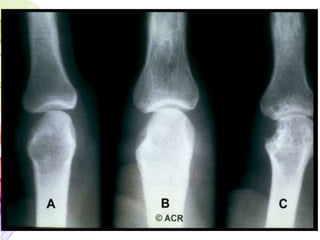

oRadiographic Features

 Peri-articular osteopenia

Uniform symmetric joint space narrowing

Marginal subchondral erosions

 Joint Subluxations

Joint destruction

Collapse